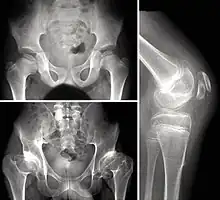

Children with autosomal dominant MED experience joint pain and fatigue after exercising. Their x-rays show small and irregular ossification centers, most apparent in the hips and knees. There are very small capital femoral epiphyses and hypoplastic, poorly formed acetabular roofs.[1] A waddling gait may develop. Knees have metaphyseal widening and irregularity while hands have brachydactyly (short fingers) and proximal metacarpal rounding. Flat feet are very common.[2] The spine is normal but may have a few irregularities, such as scoliosis.